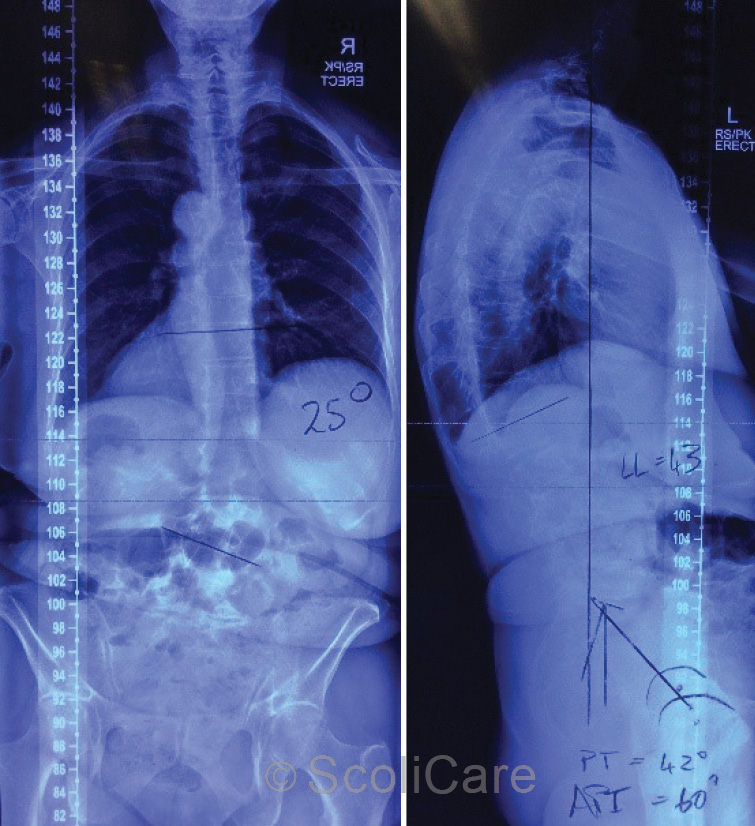

Plain films demonstrated a mild-moderate right lumbar scoliosis measuring 25° (Cobb) with an apex at L2/3 intervertebral disc (Figure 2). Extensive degenerative change in the lower lumbar spine was noted. The patient was diagnosed with progressive idiopathic scoliosis into adulthood.

Figure 2: Posteroanterior full-spine x-ray highlighting a 25° (Cobb) right lumbar scoliosis (Left),

Lateral full-spine x-ray (Right).